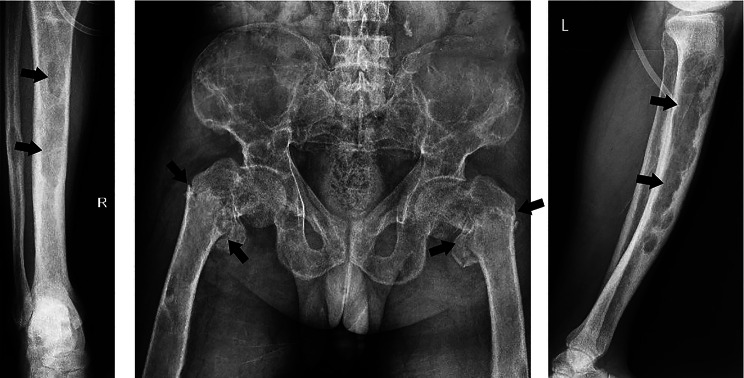

Case presentation: A 42-year-old ESRD patient on HD 3 times a week presented to Shariati Hospital, Tehran, Iran, complaining of worsening bone pain and loss of appetite. Laboratory data revealed an intact parathyroid hormone (iPTH) concentration of 2500 pg/mL, an alkaline phosphatase (Alp) level of 4340 IU/L, a phosphorus (P) level of 9 mg/dL, and a calcium (Ca) concentration of 7.2 mg/dL. Sestamibi scintigraphy revealed parathyroid adenoma. The findings suggested tertiary hyperparathyroidism (HPT-III), and the patient was scheduled for total PTX. Approximately one month after surgery, the patient was referred due to convulsions, leg mobility problems, and worsening bone pain. There was bilateral femoral ecchymosis. The Ca concentration was 5.8 mg/dL, and radiological evaluations revealed multiple skeletal fractures. HBS after PTX was suggested for this patient. After several days of hospitalization, he suffered subcutaneous emphysema followed by rib fractures and passed away.